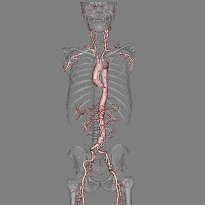

当院では東芝製マルチスライスCT、2台を使用しています。

CT造影検査も行っていますが造影する場合ヨードの副作用がある方、甲状腺疾患がある方、心疾患、肝臓、腎機能が悪い方は注意を要します。必ず主治医にご相談ください。